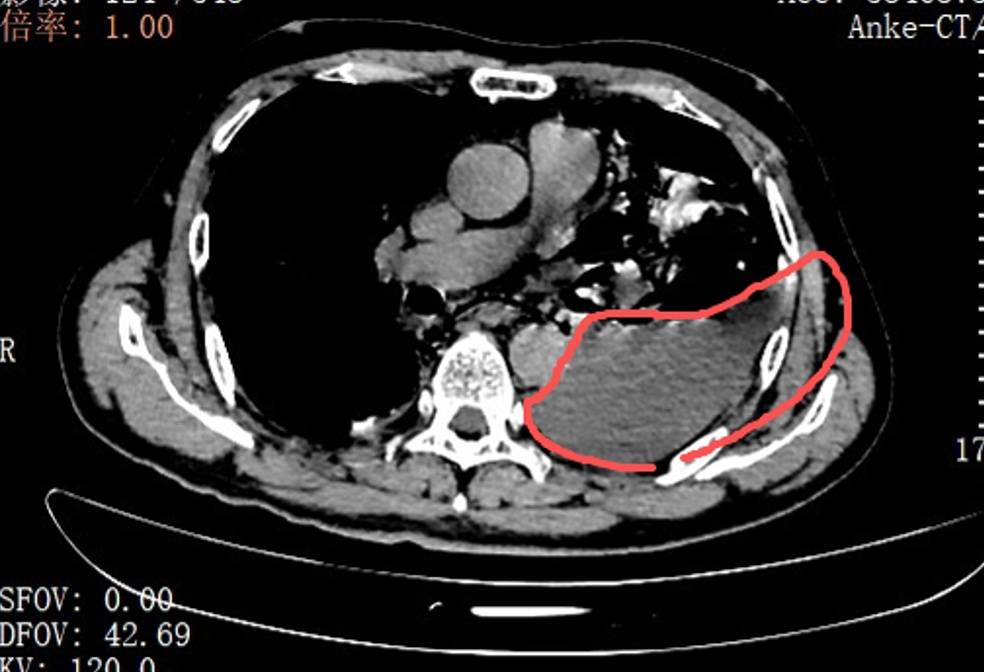

当天,手术团队为张叔实(shi)行(xing)了胸腔(qiang)镜下食道(dao)修补微(wei)创手术。打开(kai)胸腔(qiang)的那一(yi)刻,在场的医护人员都愣住了:全部左(zuo)边胸腔(qiang)里,全是叉烧包(bao)的菜叶子(zi)、食物残渣,混着(zhe)脓液和(he)消化液,到处都是。

红圈区域(yu)是食物残渣、消化液破(po)入食管(guan)

手术团队拿着(zhe)吸引器,一(yi)点点清理、冲洗,花了很长时间才将胸腔(qiang)里的每点食物残渣都清干净。随后(hou),团队找到了食道(dao)下段那道(dao)长达10公分(fen)的裂口,用可汲取线小心(xin)翼翼地完成(cheng)了分(fen)层修补。